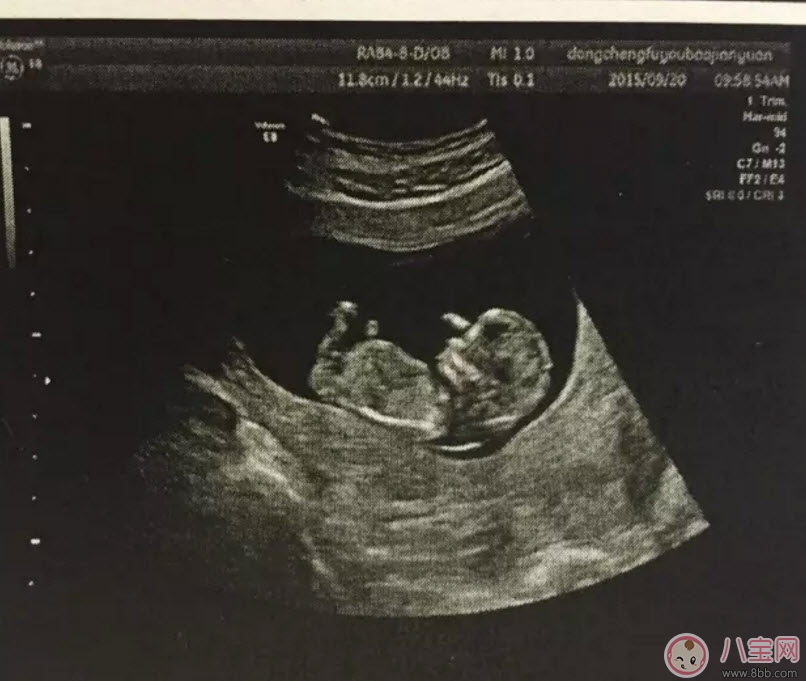

孕早期的時(shí)候用普通B超就可以了,早期只是檢測(cè)胎兒大概情況,比如檢測(cè)是否在宮內(nèi)、胎兒的頭圍、股骨長(zhǎng)、羊水等指標(biāo)。一般在懷孕8-12周做一次黑白B超確定在宮內(nèi)和胎齡。二維B超適用于孕早期。二維B超是最普通的B超,它采用的是黑白超聲診斷技術(shù),即通過超聲探頭測(cè)得的是黑白圖像,且只能觀測(cè)到胎兒的組織結(jié)構(gòu),測(cè)量出胎兒頭部、身體的長(zhǎng)度,內(nèi)臟、骨骼的大小和形態(tài),以及是否有畸形。

一般在孕中期第一次排畸的時(shí)候使用。主要是篩查胎兒各個(gè)器官是否畸形(面部及口唇除外)。第一次篩查大概是在22-24周,排查嚴(yán)重的、明顯的畸形,如果孕媽媽非常的胖,建議在26周左右再去做彩超。

一般無高危等因素或其他合并癥的孕婦妊娠期做彩色多普勒超聲或三維超聲,最好選擇在孕18~24周,因?yàn)檫@次檢查最為重要,若經(jīng)濟(jì)能力許可,選擇分辨率高的超聲儀器檢查,對(duì)胎兒生長(zhǎng)發(fā)育的觀察效果當(dāng)然更有幫助。即便如此,三維或四維的超聲檢查與其他檢查一樣并非萬能,不能代替其他的產(chǎn)前檢查方法。